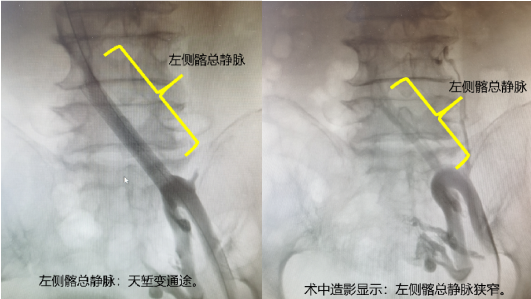

李阿婆,现年65岁,她受左下肢静脉曲张困扰有十余年,并且最近一年出现左下肢活动后水肿的症状。患者来我院就诊,张喜成主任接诊患者后,考虑患者静脉曲张,但有左侧髂静脉受压可能性。在放射科张卫国主任的指导下,该患者很快接受了CT下肢静脉造影检查。CTV图片清晰显示了李阿婆左侧髂静脉有明显受压。所以该患者的诊断明确为:左侧髂静脉压迫综合症伴有左下肢浅静脉曲张。

通常来说,针对此次治疗需要进行两台手术:先在DAS下行髂静脉成形术,以缓解压迫症状,再在手术室进行曲张静脉治疗。我科对该患者病情综合讨论后,决定采取复合手术,在同一次手术中解决李阿婆的两个血管问题。手术由张喜成主任和黄献琛副主任共同为患者施行。采用神经阻滞麻醉,在很小的切口下暴露出大隐静脉,通过这个入路,对髂静脉进行血管扩张,植入支架以后髂静脉随即恢复通畅,最后向下采用微创激光治疗的方法处理下肢的曲张静脉。手术在导管室老师的配合下进行顺利。